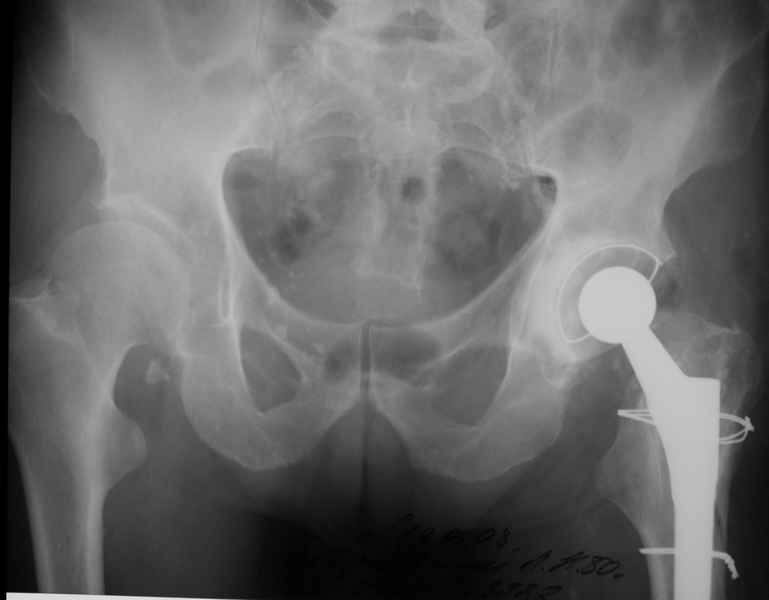

Хочется показать два подобных случая, П-ка З. 72 лет и п-т Г. 80 лет. Сразу принимаю замечание, что это были ножки цементной фиксации, просто под руками не было бесцементника.